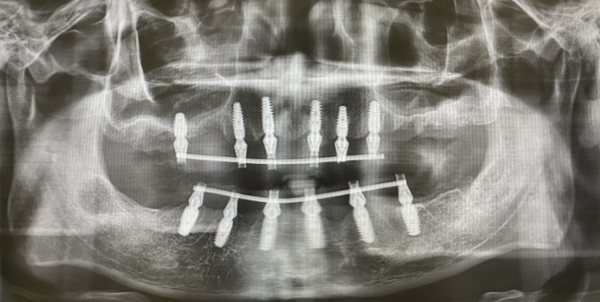

牙周炎导致全口牙松动 博爱曙光医生帮换牙

深圳博爱曙光医院还正式开放“牙缺失门诊”。